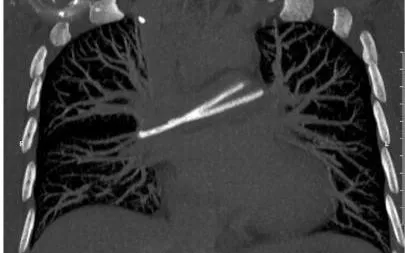

Trong một lần khám tầm soát, kết quả chụp CT ngực phát hiện hình ảnh dị vật nằm trong tim, vắt ngang vùng chia hai nhánh động mạch phổi. Qua thăm khám chuyên sâu, các bác sĩ ghi nhận catheter đã bị đứt: một đoạn còn nằm dưới da vùng dưới xương đòn phải, đoạn còn lại đã di chuyển vào tim và động mạch phổi. Người bệnh được chuyển đến Bệnh viện Quân y 175 để xử trí can thiệp tim mạch.

Theo ThS.BS Hoàng Hải Anh, Khoa Can thiệp tim mạch, đây là trường hợp rất hiếm khi dị vật không chỉ nằm trong tim mà còn đi sâu tới động mạch phổi, khiến việc xử trí phức tạp hơn nhiều. Ekip đã lựa chọn phương pháp can thiệp nội mạch qua đường tĩnh mạch đùi, sử dụng dụng cụ chuyên dụng tiếp cận tim và động mạch phổi để gắp dị vật ra ngoài, tránh phẫu thuật mở ngực nhiều nguy cơ.